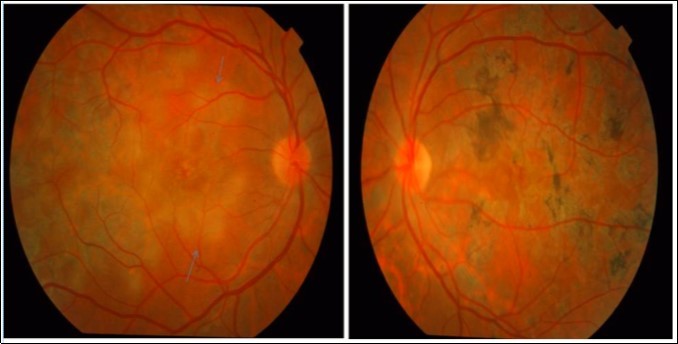

A 34-year-old male presented with decreased vision in Right eye since one and half month. On examination, the BCVA was 6/ 60 and 6/6 in the right and left eyes, respectively. Both eyes showed unremarkable anterior segment and multifocal lesions of active as well as inactive choroiditis in the posterior pole of Right eye and healed choroditis on left eye (Figure 1). Simultaneous FAF and SD-OCT imaging of the right eye revealed findings as explained in the “Results” Section (1.) (Figure 2). The tuberculin skin test was positive. He received four-drug antitubercular therapy with oral corticosteroids. About 2 weeks later, the lesions started to heal and appeared as described in “Results” Section (2.) (Figure 3). Three months later, the lesions healed further and appeared as explained in “Results” Section (3.) (Figure 4). Figure 5, Figure 6.

Figure 1.Color photograph of the right eye of patient 1shows an active MSC (blue arrows) and left eye shows healed MSC from her initial visit